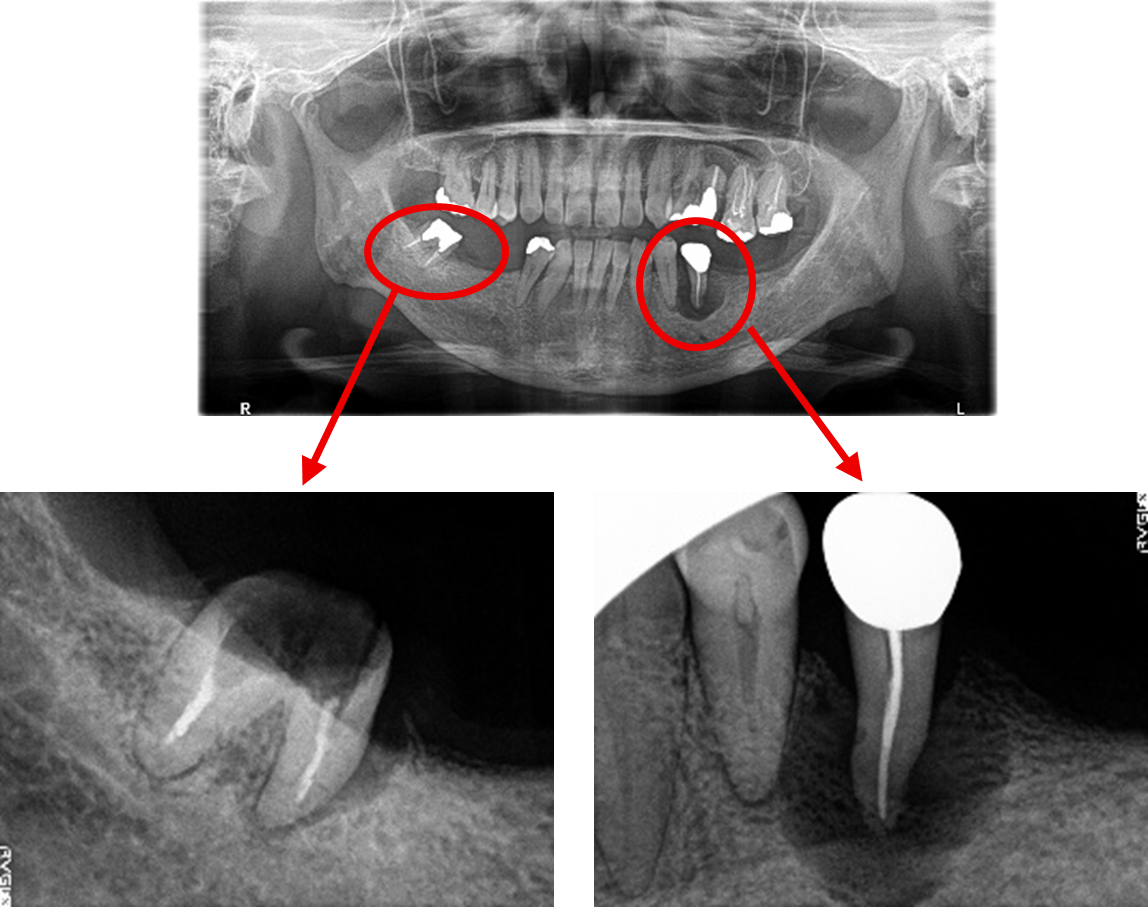

Before

※赤丸は、歯根が破折していたため抜歯しました

※黄色丸は、2006年10月に埋入したインプラント